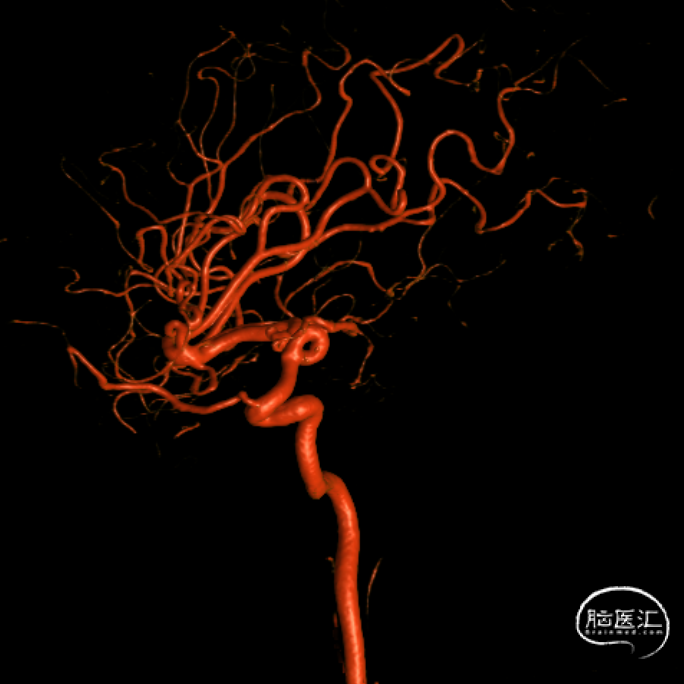

CT(CTA)检查提示:右颈内动脉C7段大小约3.6×3.8×3.6mm及基底动脉远端动脉瘤形成大小约9.7×7.6×9.3mm。

DSA:右侧P1段一6.8*9.7mm不规则囊状突起动脉瘤,远端P2段呈螺旋状蛇形动脉瘤改变。

DSA:右侧P1段一6.8*9.7mm不规则囊状突起动脉瘤,右侧A1段动脉瘤。夹层蛇形动脉瘤。

DSA:评估右侧后交通。

右侧颈内正位

右侧颈内3D

椎动脉压颈3D